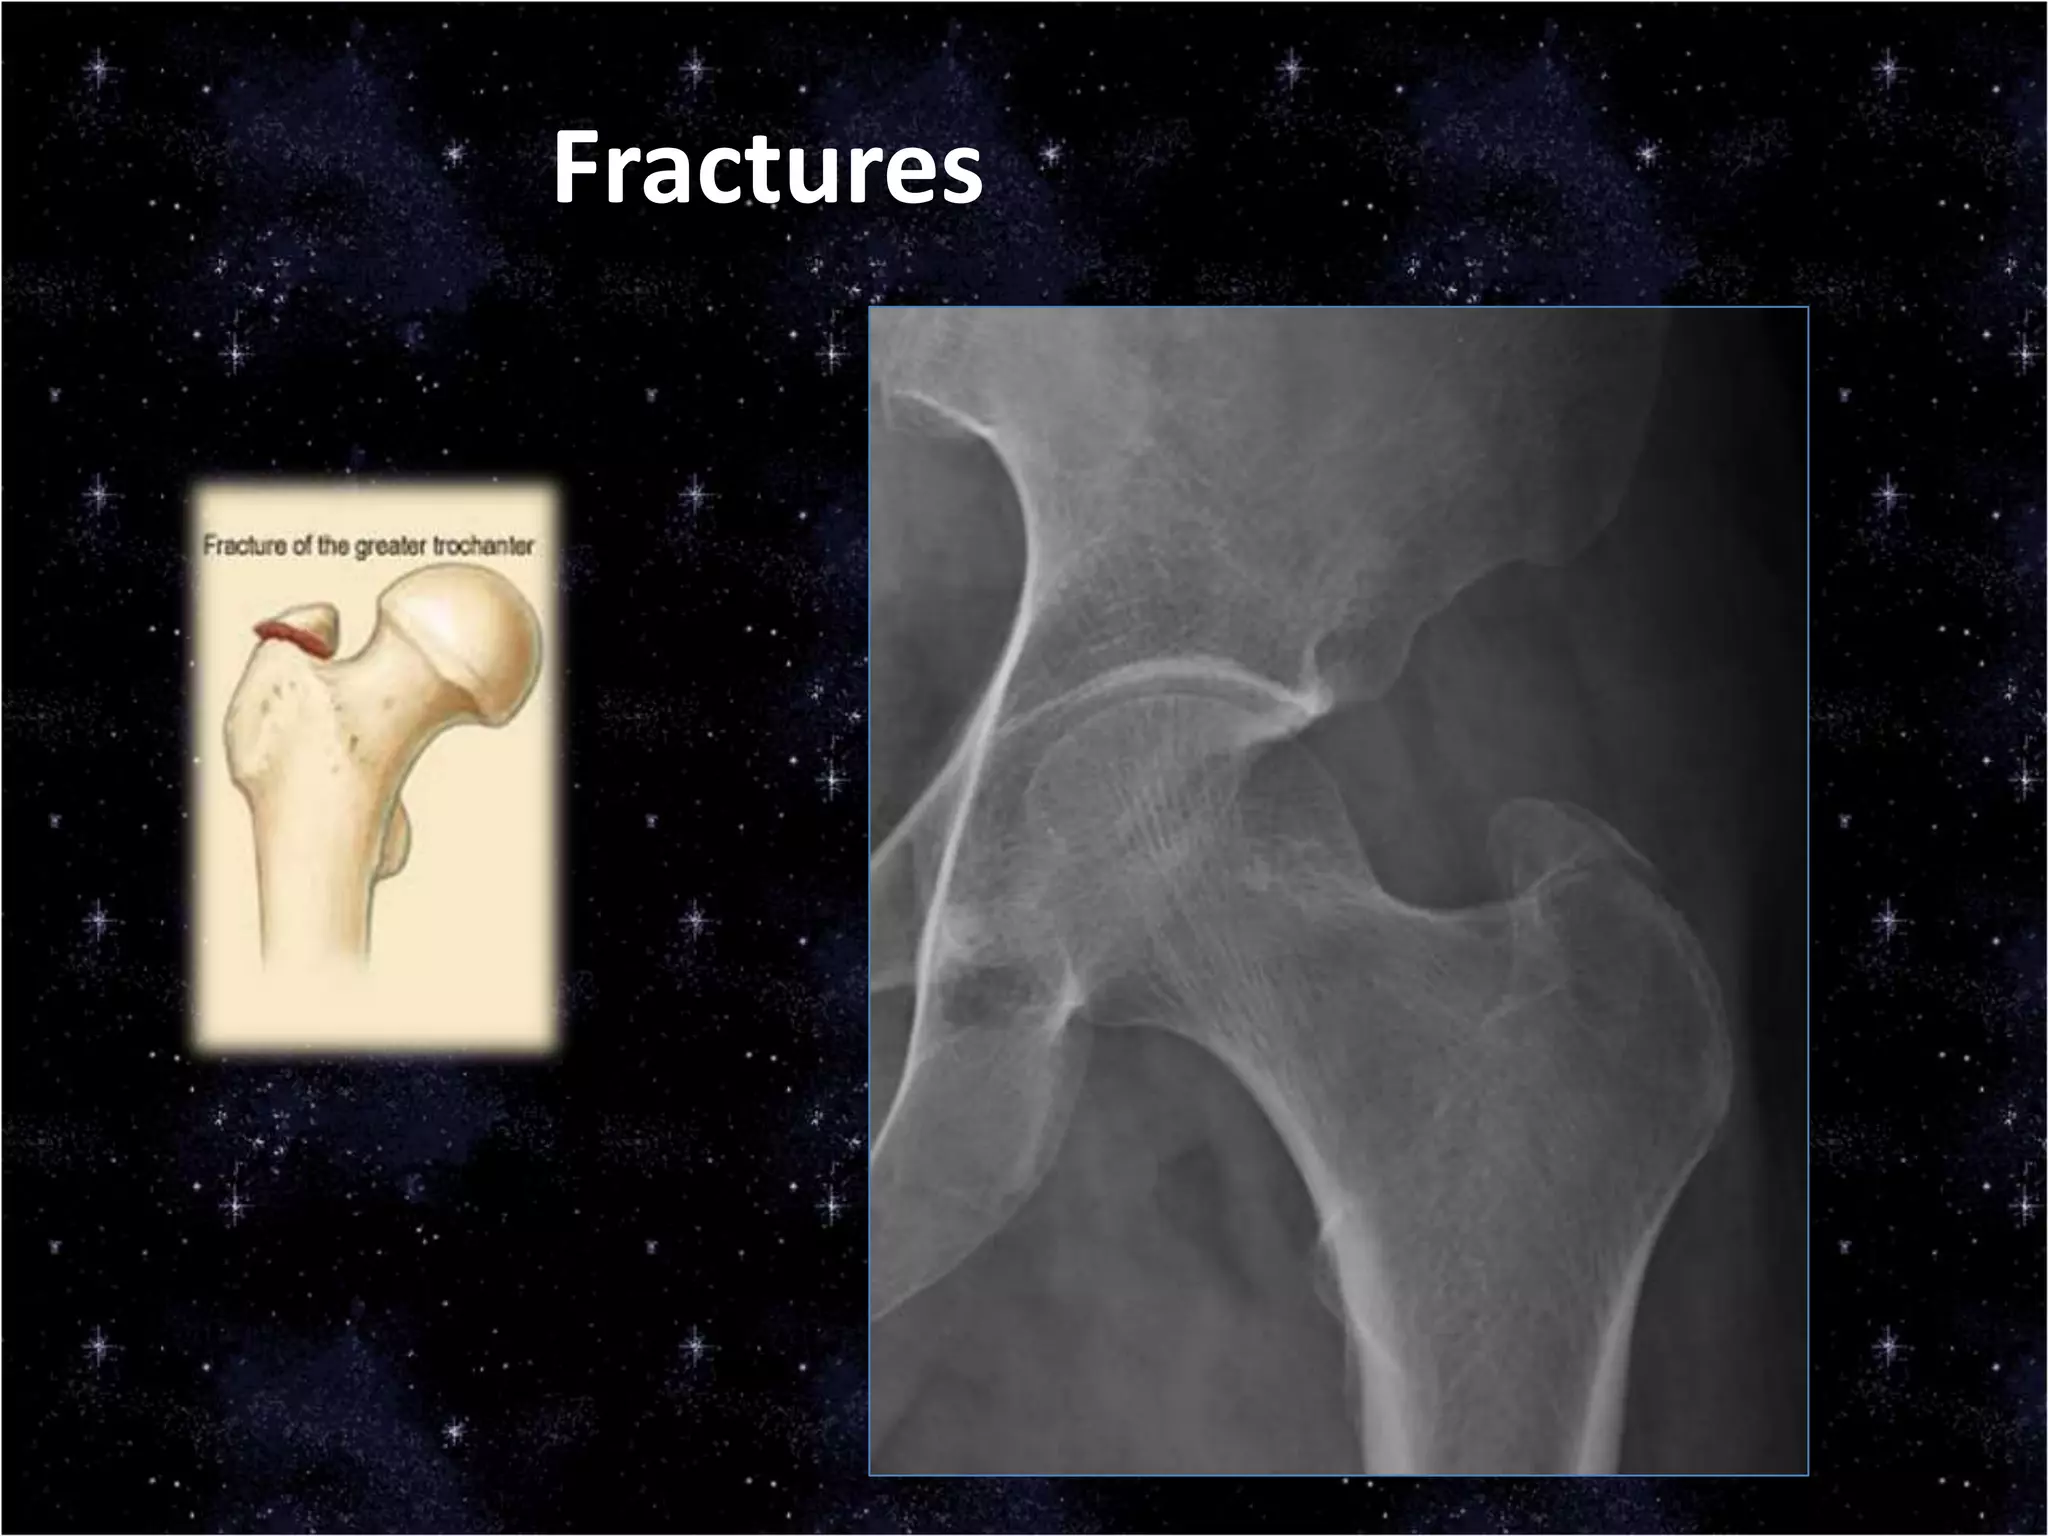

This document discusses trauma to the pelvis, hips, knees, ankles, and feet. It covers anatomy, imaging techniques, and types of fractures and dislocations that can occur in these areas. The types of fractures discussed include pelvic ring fractures, acetabular fractures, and fractures of the femur, tibia, fibula, and bones of the foot. Imaging views used include AP, inlet, and outlet views of the pelvis. Dislocations and fractures of the knee, ankle, and foot joints are also examined.